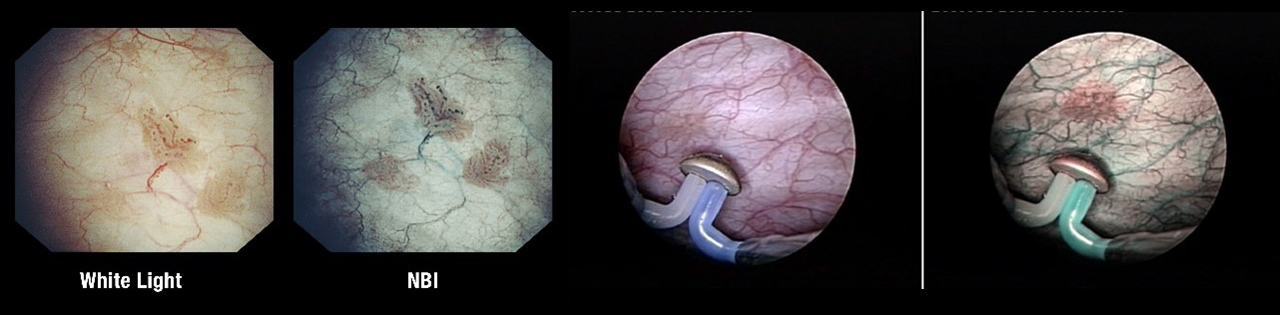

Разновидности цистосокпов:

Вид опухоли при цистоскопии:

Стандартная цистоскопия обычно выполняются при так называемом «белом» освещении. Однако, некоторые образования могут оставаться невидимыми при таком освещении, что привело к разработке новых методов визуализации опухоли.

Один из таких методов — это узкополосная визуализация (NBI). Исследования показали, что использование NBI при осмотре мочевого пузыря значительно увеличивает частоту выявления рака.